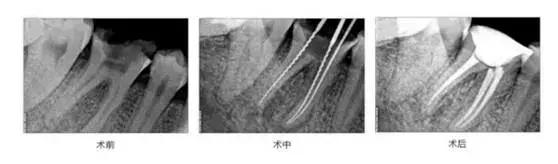

根管治疗

这种治疗一般是由于虫牙经过日积月累感染到牙髓组织引起炎症,进一步形成根尖周炎;或是外伤导致牙齿折断,牙神经已经暴露在外,但牙根尚在进行的修复治疗。因为牙神经是很敏感的组织,出现问题或者暴露在外面时,会引发牙齿疼痛等问题,留下隐患,所以通过根管治疗进行保留患牙。